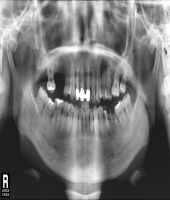

| ● 진료과목 : [임플란트] 치주환자의 보철치료

| ● 내용 : 60대 치주환자의 보철치료 |